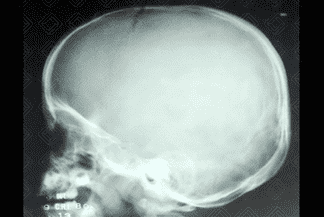

Texto alternativo para a imagem Figura 1. Crédito: Dra. Elazir Mota - Rio de Janeiro/RJ

Texto alternativo para a imagem Figura 2. Crédito: Dra. Elazir Mota - Rio de Janeiro/RJ

Descrição da lesão: Cisto dermoide. Radiografia de crânio AP e perfil (figuras 1 e 2): lesão ovalada, bem definida, na linha média, adjacente à sutura sagital e metópica.

• Radiografia do crânio: Lesão ovalada, bem definida, em geral adjacente as suturas;